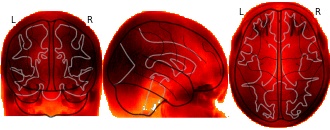

(2018). Longitudinal Analysis of Image Time Series with Diffeomorphic Deformations: A Computational Framework Based on Stationary Velocity Fields: Study-specific template [Dataset]. http://identifiers.org/neurovault.image:16308

glassbrain

Collection description

Subject species

homo sapiens

Modality

Structural MRI

Cognitive paradigm (task)

None / Other

Map type

A